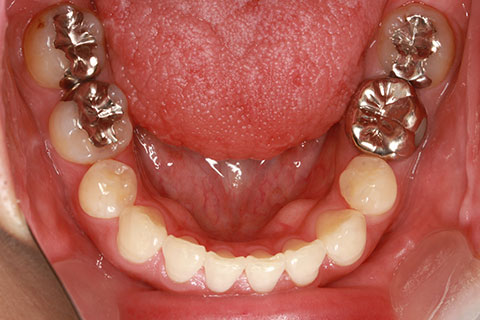

症例

治療前

治療中

治療後

- 年齢・性別

- 30歳女性

- 治療期間

- 3年0ヶ月

- 抜歯

- 上下左右4番抜歯

- 治療費

- 110万円

- 備考

- マルチブラケットを用いた矯正治療

- 治療内容

- 上下顎前突を4本抜歯にて矯正治療

- 施術の副作用(リスク)

- 表側矯正と比較して、歯根の角度を確立する「トルク」の力がかかりにくい。